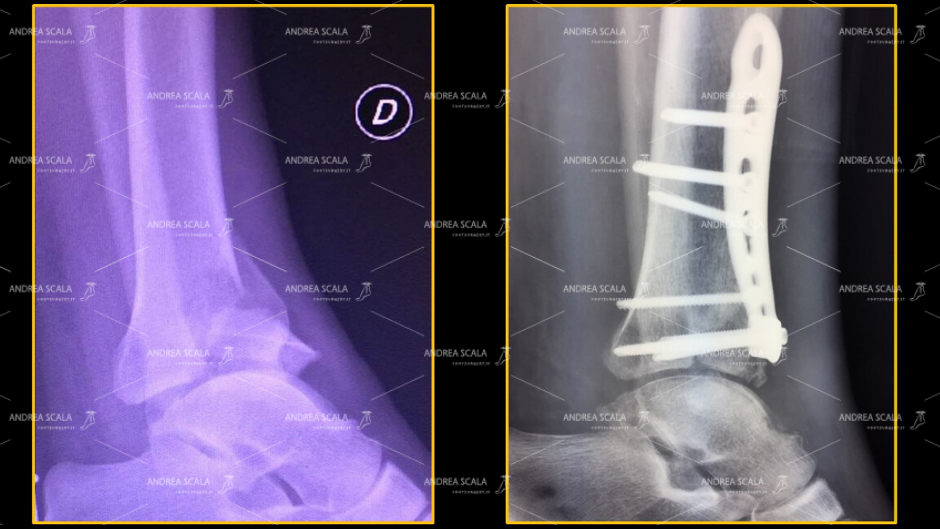

La FRATTURA DEL PILONE TIBIALE. Con frattura del pilone tibiale si intende una lesione scheletrica a carico della regione meta–epifisaria distale della tibia, che comprometta la quasi totalità della superficie articolare tibiale sottoposta al carico, e che è associata frequentemente ad una frattura del perone.

2) FRATTURA DELLA TIBIA E DEL PERONE La grande varietà delle fratture scheletriche vengono comprese in diversi sistemi di classificazione che tengono conto della localizzazione anatomica delle fratture, del coinvolgimento della superficie articolare della tibia ( “PLAFOND TIBIALE” ), energia del trauma , coinvolgimento dei tessuti molli, esposizione della frattura.

La principale regola chirurgica è quella di cercare quanto più possibile la riduzione anatomica dei frammenti della frattura. Questa regola diventa un obbligo nei casi di frattura delle articolazioni, come avviene per tutte le fratture che coinvolgono le articolazione dello scheletro.

I risultati clinici a distanza non sono omogenei e risultano molto variabili anche in centri traumatologici di grande esperienza. Molto spesso si osservano interventi molto ben eseguiti in cui la frattura risulta ricomposta molto bene con placche e viti disposte in modo adeguato, in cui la mobilità articolare il risultato funzionale risultano molto deludenti sia per il paziente che per il chirurgo.

La frattura risulta ricomposta molto bene con placche e viti disposte in modo adeguato, in cui la mobilità articolare il risultato funzionale risultano molto deludenti sia per il paziente che per il chirurgo.